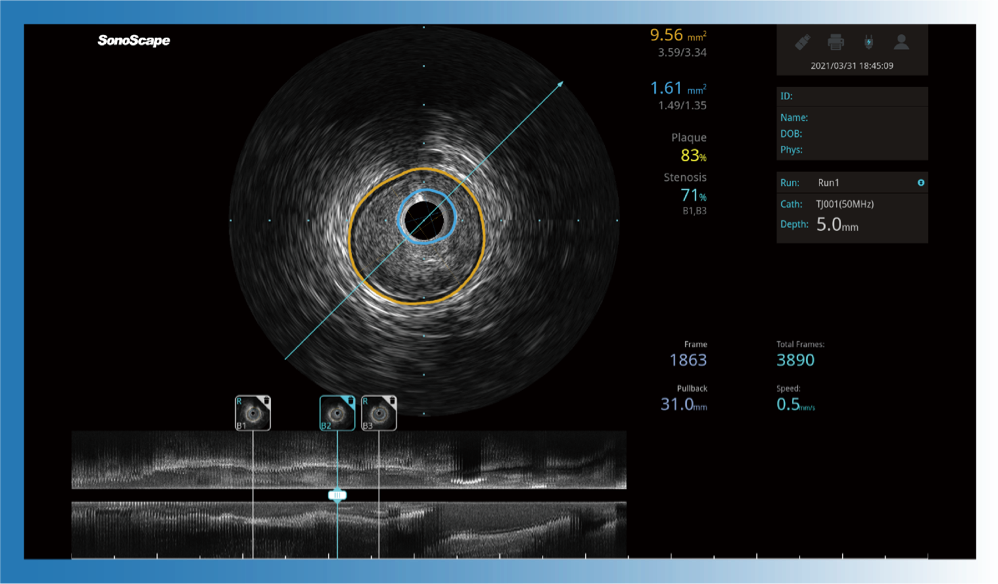

治療前后兩次測(cè)量錄像對(duì)比

簡(jiǎn)化療效評(píng)估

一鍵智能描跡,自動(dòng)測(cè)量斑塊負(fù)荷、面積狹窄率等指標(biāo),準(zhǔn)確率高于90%